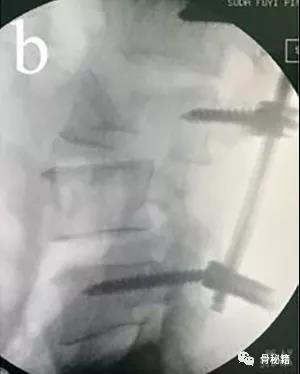

撑开时,可先用直棒,最后复位好了后再进行棒的塑性恢复腰椎前凸来达到较好的稳定

最后添加横联和植骨融合来增加稳定性